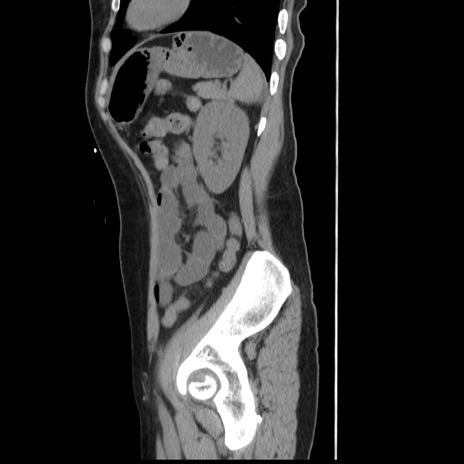

症例10(矢状断像)

【症例】 50歳代女性

【主訴】 腹痛

【現病歴】前日生レバーを食べた。今朝に排便あり。 昼前に突然発症の腹痛を生じ、当院救急外来を受診した。

【既往歴】 子宮筋腫にてで子宮全摘後

【身体所見】 意識清明、腹部:平坦、軟、下腹部やや左を中心に圧痛・反跳痛あり、筋性防御あり

【データ】WBC 7800、CRP 0.07